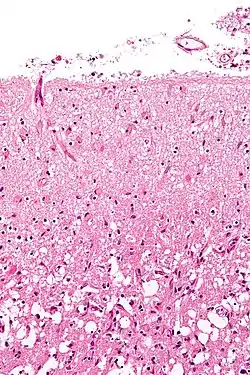

Hemorrhagic

Hemorrhagic strokes are classified based on their underlying pathology. Some causes of hemorrhagic stroke are hypertensive hemorrhage, ruptured aneurysm, ruptured AV fistula, transformation of prior ischemic infarction, and drug-induced bleeding.[61] They result in tissue injury by causing compression of tissue from an expanding hematoma or hematomas. In addition, the pressure may lead to a loss of blood supply to affected tissue with resulting infarction, and the blood released by brain hemorrhage appears to have direct toxic effects on brain tissue and vasculature.[43][62] Inflammation contributes to the secondary brain injury after hemorrhage.[62]